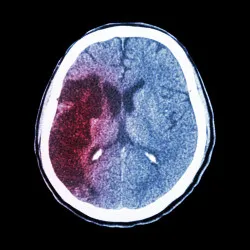

The anticoagulant effect of Eliquis may be linked to an increased risk of bleeding on the brain, a condition sometimes referred to as hemorrhagic stroke. This type of brain bleed is different from the kind of stoke Eliquis is meant to prevent, known as an ischemic stroke.

A brain bleed results not from a clot blocking blood flow to the brain but from damage to a blood vessel that results in bleeding within or on the outside of the brain.